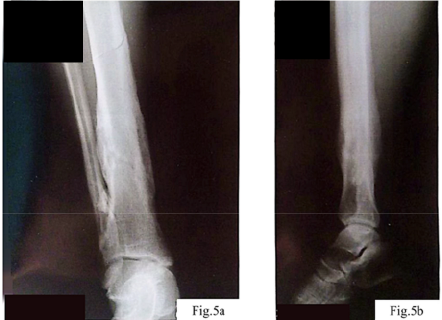

Considering the nature of the fracture and the need for stable fixation of the fragments, a decision was made to perform open osteosynthesis using metal plates, as shown in Figure 2. The surgical treatment was delayed for two weeks due to implant supply interruptions associated with the military conflict in Ukraine. During the operation, two metal plates with a total of 16 screws were implanted, the wound was closed in layers, and four drains were placed to control postoperative fluid outflow.

a – Anteroposterior view of the tibia following osteosynthesis with two metal plates; b – Lateral projection showing fixation with 16 screws securing the plates.; c – Follow-up lateral X-ray demonstrating correct positioning of implants; d – Control X-ray confirming stability of the osteosynthesis construct